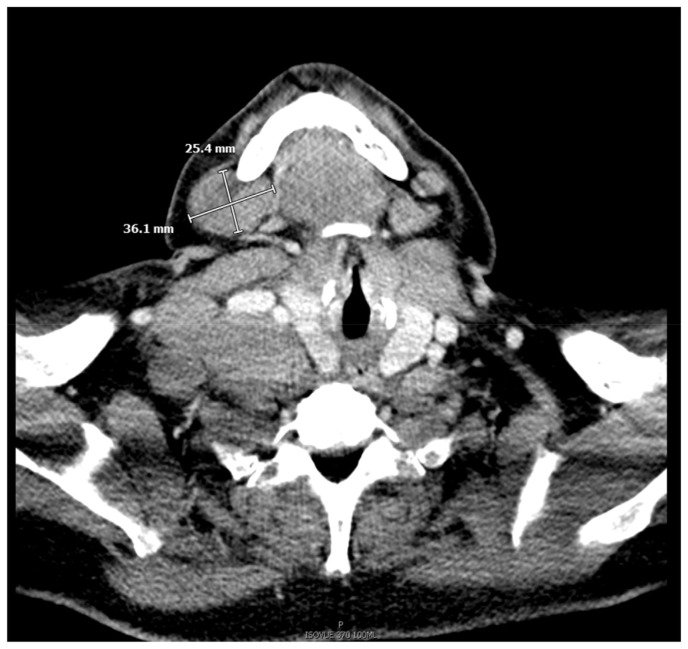

Marginal Zone Lymphoma in a Case of Hidradenitis Suppurativa Treated With Adalimumab Therapy.

Marginal zone lymphoma has seldom been described in relation to adalimumab used for treatment of hidradenitis suppurativa. Although studies have shown an increased risk of lymphoma with adalimumab, most of these studies were done in patients with underlying inflammatory bowel disease or rheumatoid arthritis where the disease itself presents as a confounder for lymphoma. Our case described adds to the role of chronic anti-TNF alpha therapy as a possible etiology of lymphoma.